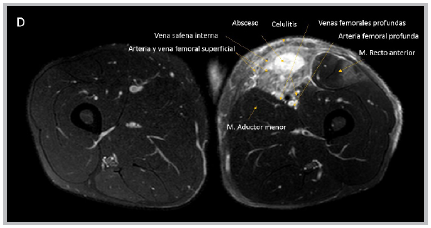

Figure 1 A: a photograph of the anterior internal aspect of the left thigh showing an abscess in the vertex of Scarpa's triangle. B: magnetic resonance imaging, coronal section, C: sagittal section showing an abscess and area of pyomyositis in the left thigh..

Pyomyositis 1 is an acute bacterial infection of the skeletal muscle with abscess formation. The incidence is 33-40%, mainly in young adult males. Staphylococcus aureus is responsible for 90% of the cases 2. It occurs due to dissemination from a distal infection or direct extension from an adjacent process. It has three phases: a) invasive: one to two weeks; b) purulent: the next 1021 days (90% of the patients consult at this stage); and c) systemic inflammatory response 3. A culture of the secretion and diagnostic ultrasound are required 4; magnetic resonance imaging is the test of choice 5. It is initially treated with antibiotics and requires surgical drainage in the second and third stages. Broad spectrum coverage is used in patients with comorbidities or immunosuppression, including Gram negative and anaerobic coverage. The reported mortality ranges from 2 to 20%, and is highest in patients with comorbidities.